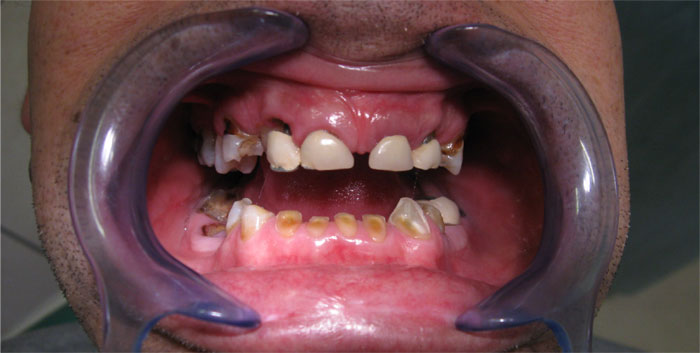

Nachfolgend finden Sie Fotos und Interview-Videos von Patienten, die in der Klinik Europa Dental implantatgetragene Brücken haben machen lassen.

Fall Nr. 1: Brücke auf Alpha-Bio-Implantaten und Brücke auf natürlichen Zähnen